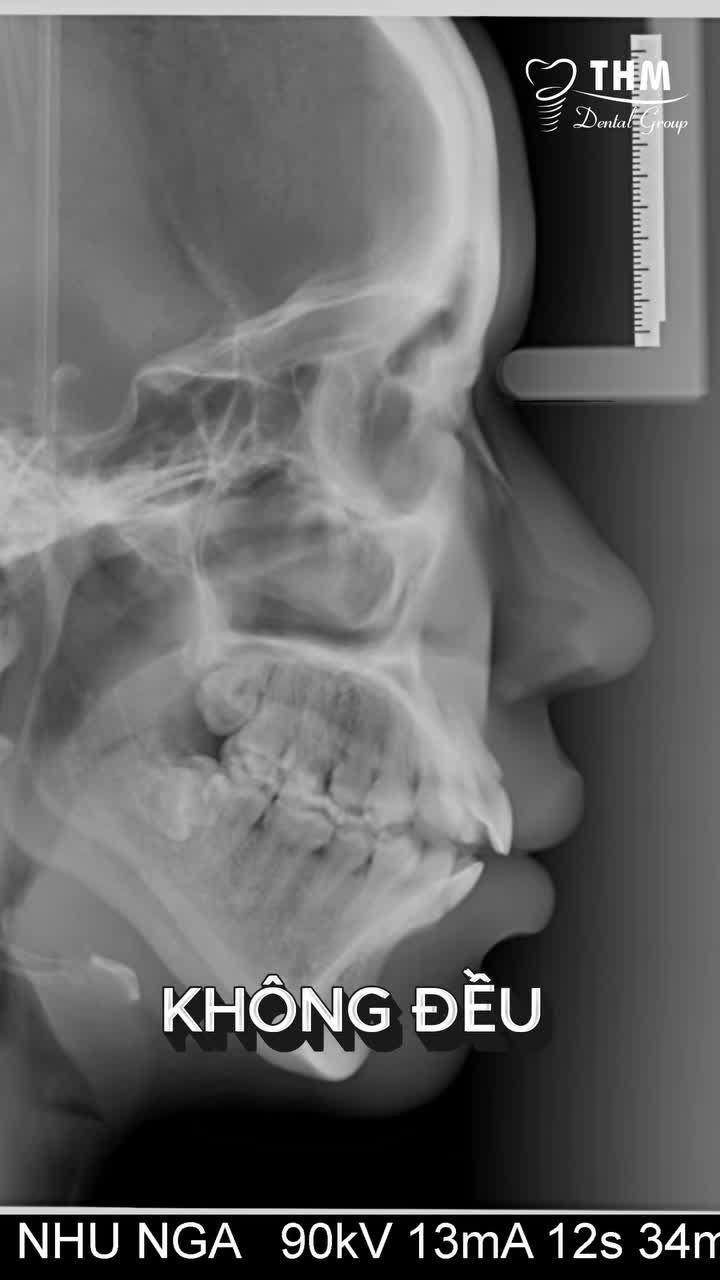

Hôm nay, bệnh nhân đến gặp BS CKI Nguyễn Phương Thảo với tình trạng:• Hô răng hàm trên• Độ cắn chìa 6mm làm hàm dưới lùi sâu• Xuất hiện tiếng kêu ở khớp thái dương hàm• Hàm dưới lùi gây áp lực trực...